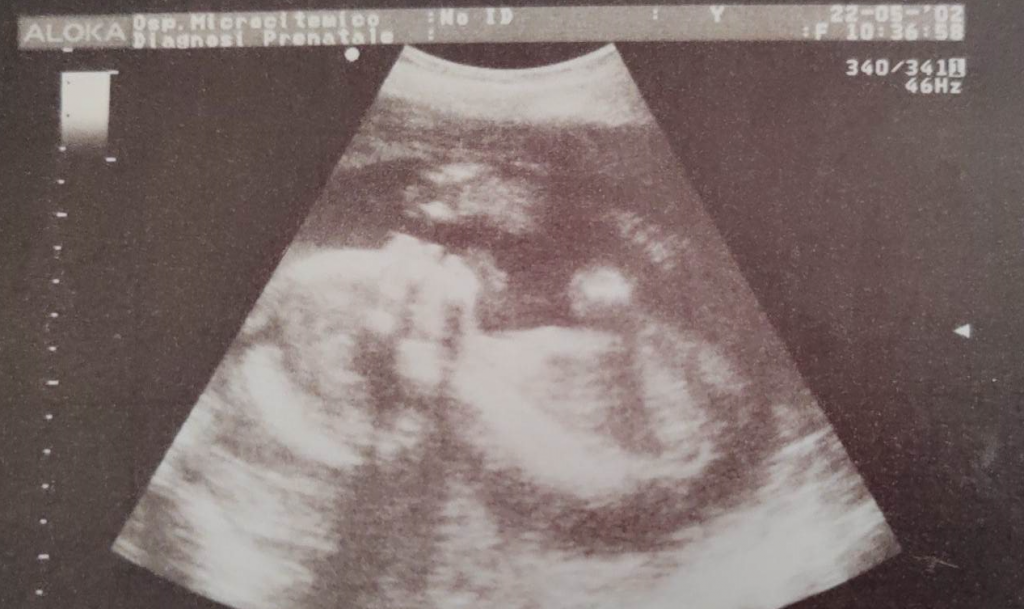

Da femminista quale sono, rivendico i diritti delle donne e il diritto di poter scegliere sulla propria vita. Una gravidanza portata a termine è un piccolo essere vivente che crescerà, avrà bisogno di cure, attenzioni e tutto ciò che serve ad una persona per vivere. Quello che nelle prime settimane è un cumulo di sangue, diventerà in nove mesi un bambino, che sarà un adulto come tutti noi. Metterlo al mondo comporta delle responsabilità, non tutte le donne hanno i mezzi per portare avanti una gravidanza. E preferisco non entrare nel merito dei mezzi che possono essere materiali o immateriali.

Ma quando l’aborto diventa un problema? Diventa un problema quando è il piano B per evitare una gravidanza; quando diventa un contracettivo; quando viene preso alla leggera guardando quel piccolo grumo di sangue come se fosse un brufolo da eliminare. Allora sono d’accordo, la legge 194 va rivista e dettagliata meglio. Sono del parere che la gravidanza rappresenti la vita e vada tutelata, così come va tutelato il bambino, o bambina, che sarà pronto a nascere alla fine delle 40 settimane di gestazione.